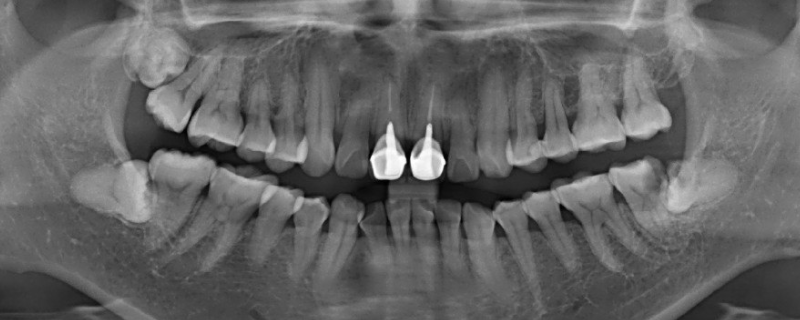

冠周在牙冠周围,冠指牙冠,就是牙齿暴露出来的部分,周是周围的意思,综合就是牙冠周围的意思。冠周炎一般是指智齿牙冠周围软组织发生非特异性炎症,如果发生身体不适的症状,应及时到医院就诊。冠周炎考虑是经常挑食、偏食,可能会使身体摄入的营养元素不足,导致全身抵抗力下降,使细菌在牙冠周围繁殖,出现牙龈肿胀、疼痛的情况。